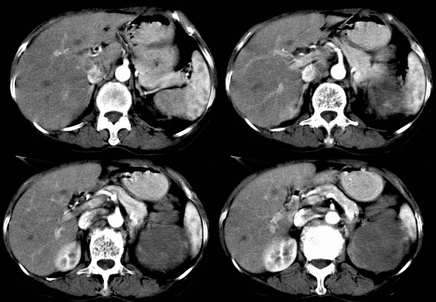

左肾不规则软组织肿块,内见低密度坏死区,与正常肾实质分界不清,左肾明显增大,增强呈不规则条索状强化,肾盂及左输尿管上段扩张。肾周脂肪层受侵、模糊。印象:典型左肾癌。

平扫,表现为肾实质肿块,呈分叶状,肿块密度不均,内有不规则低密度区(陈旧性出血?坏死?)有的似呈囊性,增强明显不均一强化,与肾实质相比呈相对低密度的不均一肿块,肾周脂肪间隙可见,肾前筋膜未见增后,肾血管及腹主动脉旁未见肿大淋巴结影

左侧肾癌并肾静脉癌栓.腹膜后淋巴结肿大转移.

左肾癌累及左输尿管,左肾静脉无受累征象。